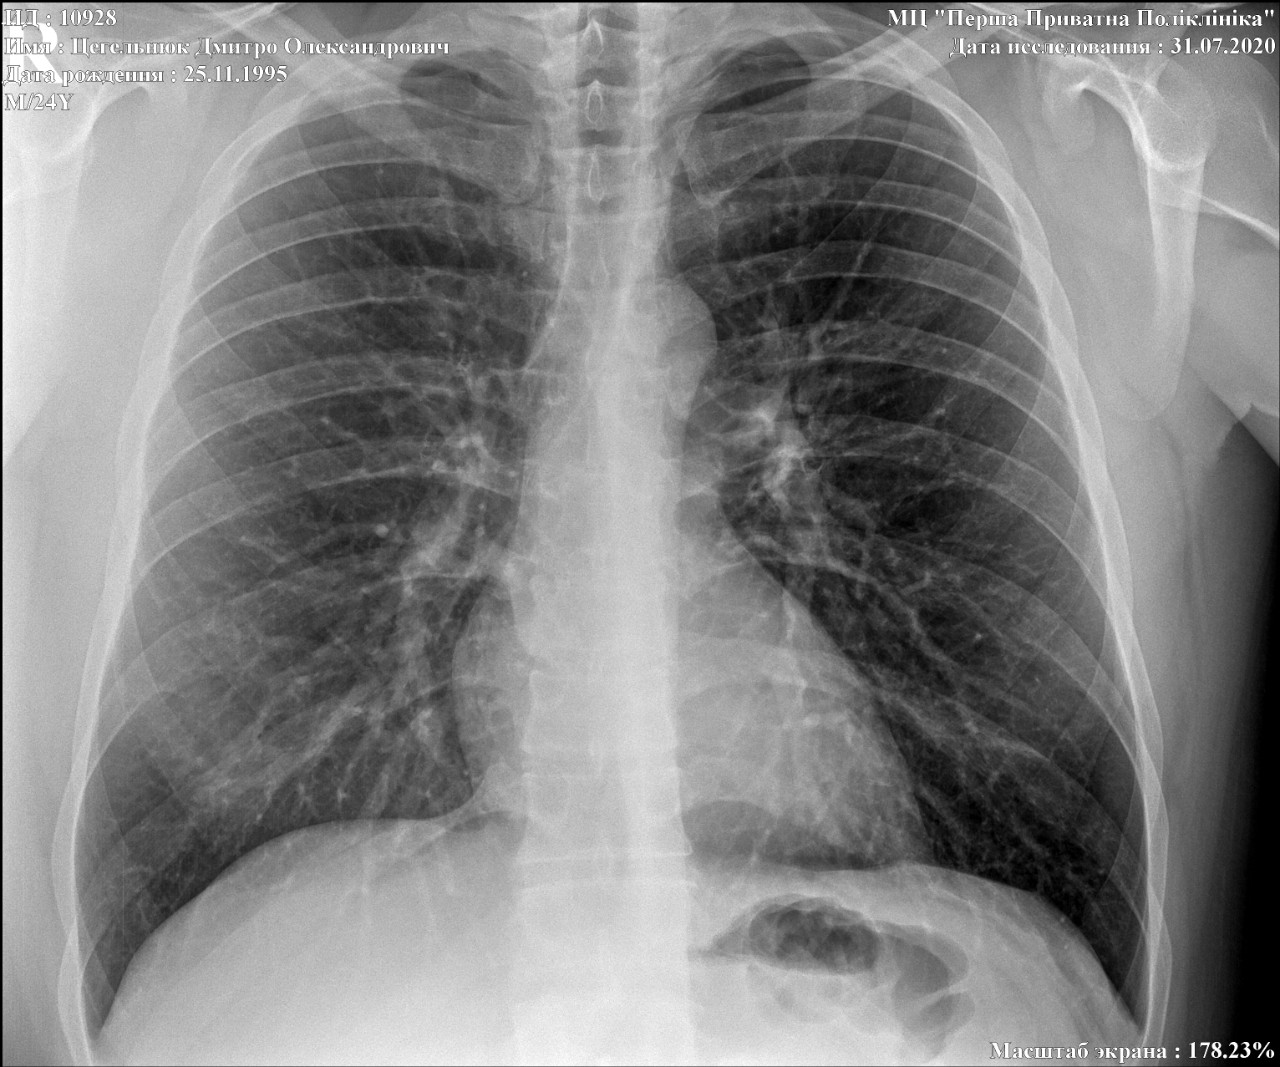

Нормальная рентгенограмма легких: что нужно знать